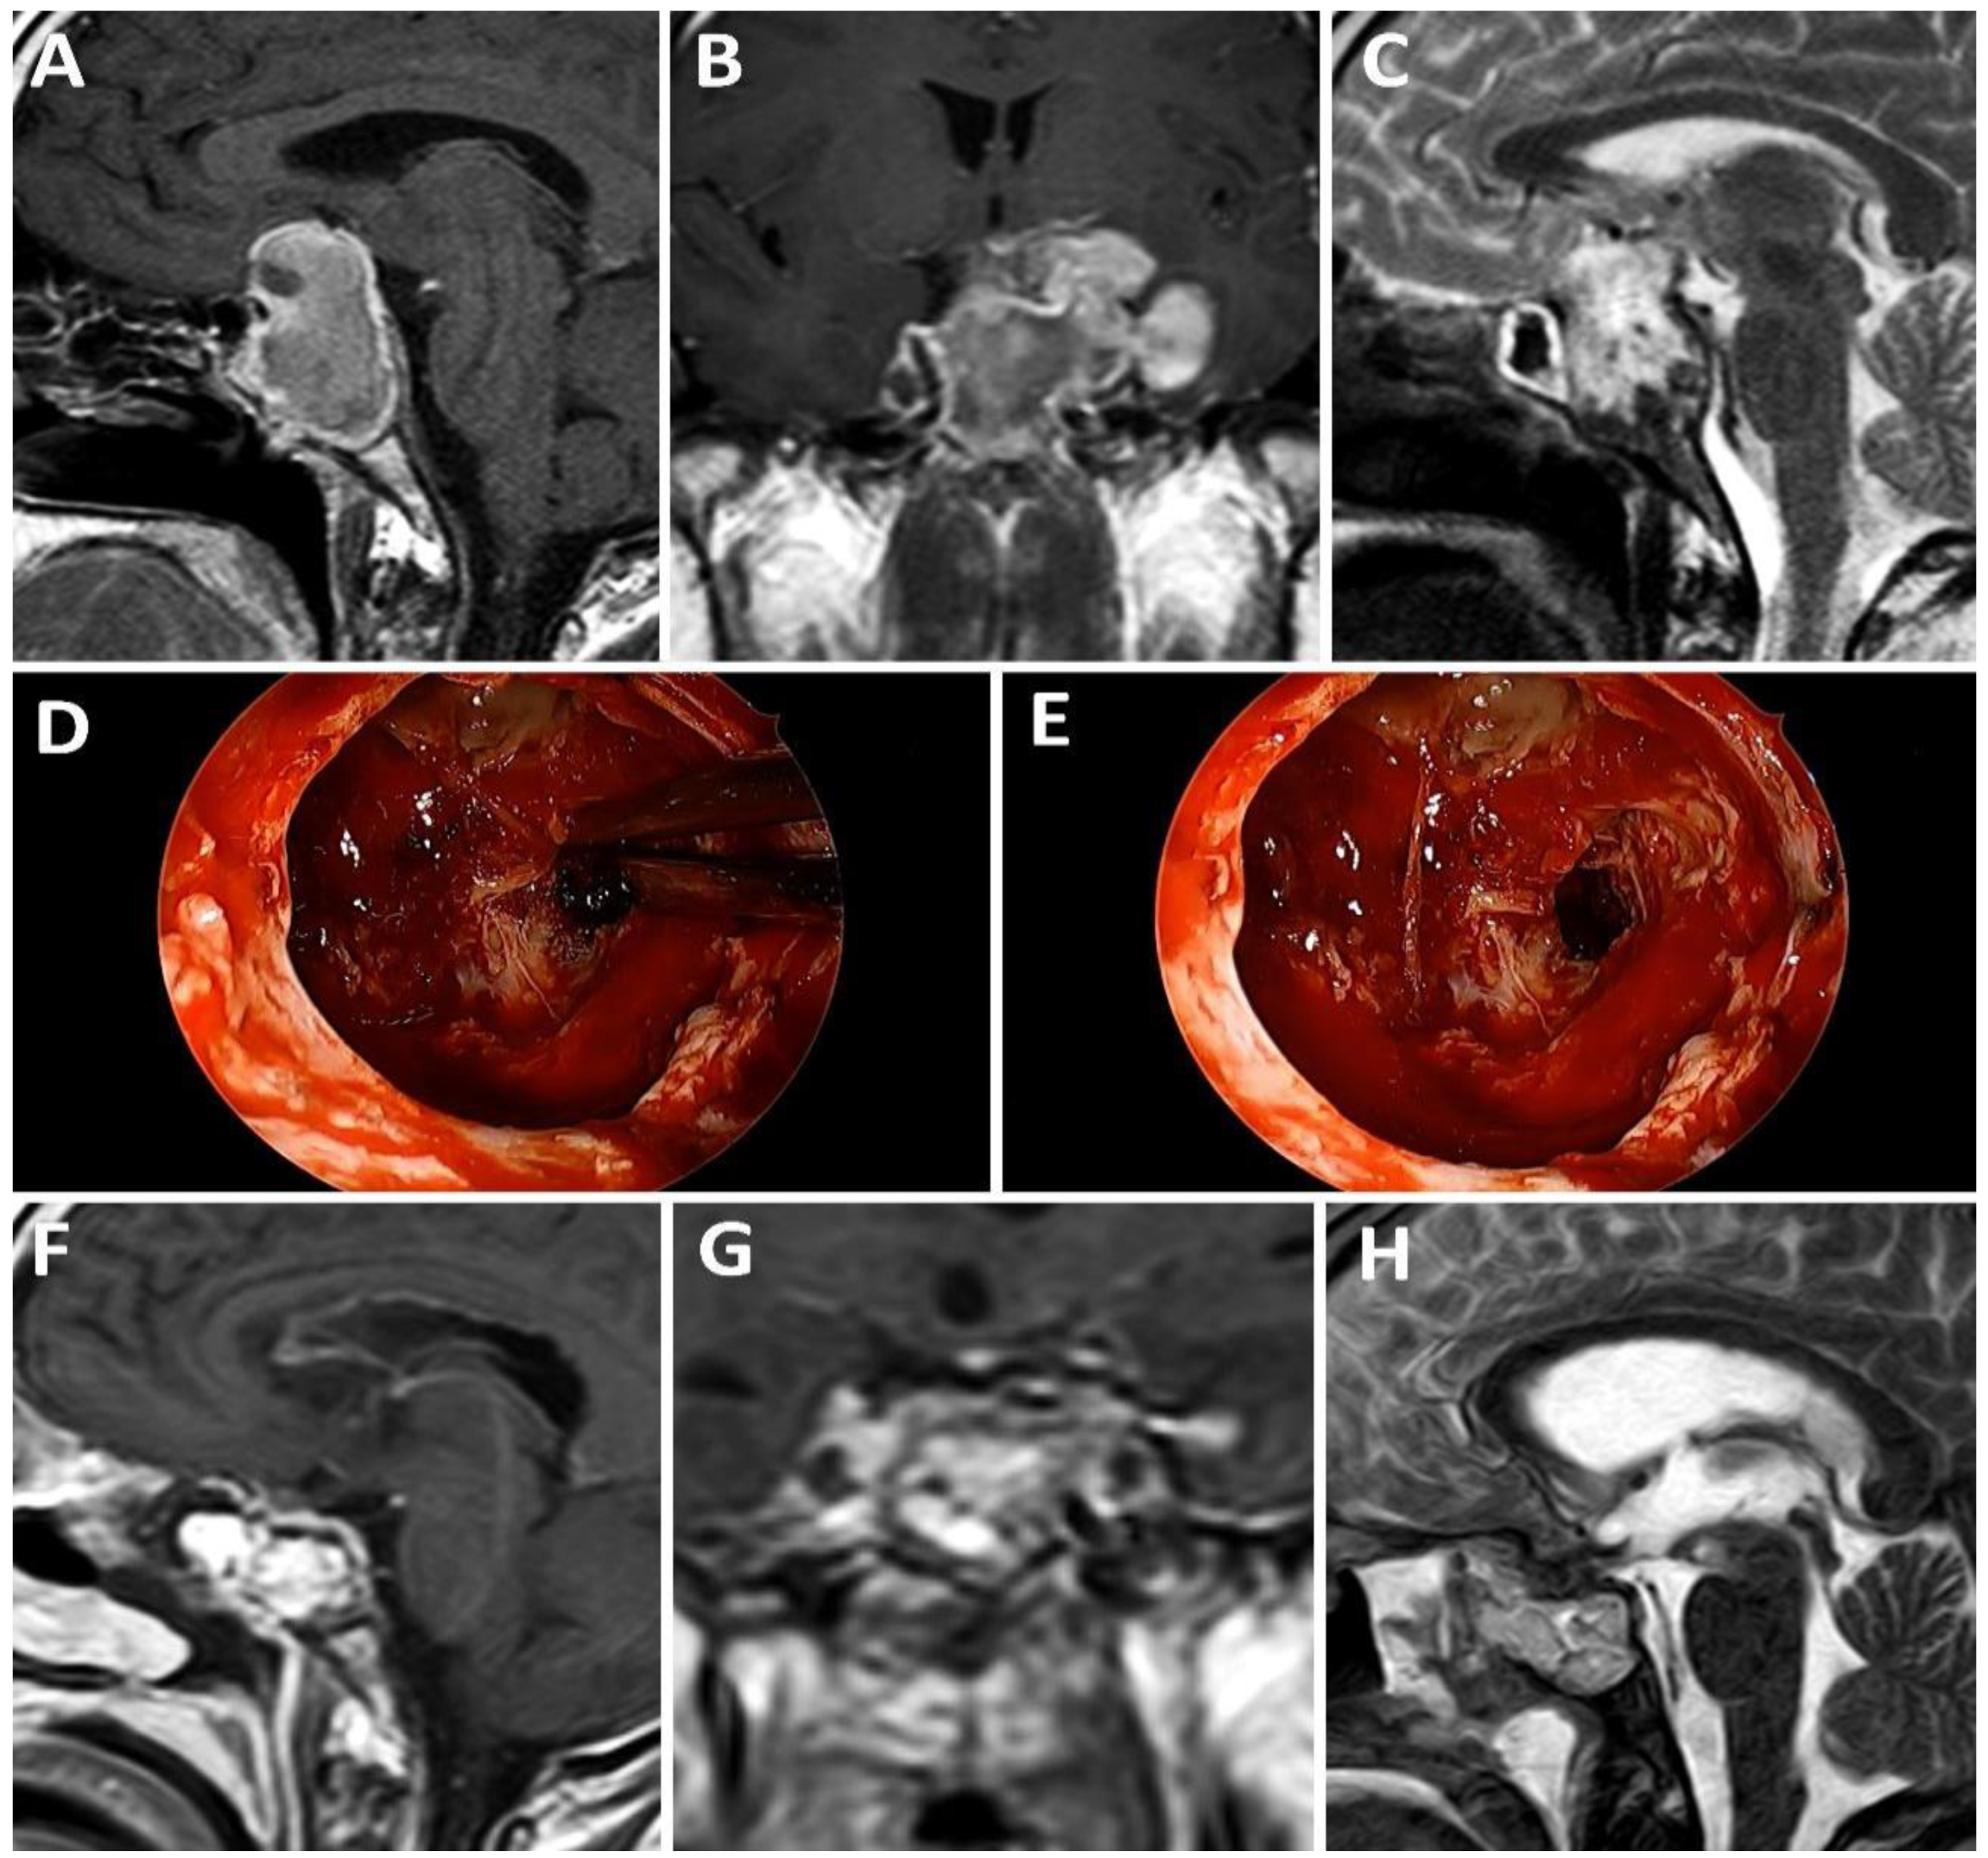

4.2.5. Differentiation Sellar Barrier Subtypes on MRI and during Surgery

- -

- Strong: barrier thickness more than 1 mm.

- Weak: barrier thickness less than 1 mm.

- Mixed: T1-weighted volumetric sequences displaying both types of thicknesses in different areas of the sellar barrier.

- Strong: gland and/or dura mater are observed on the roof of the pituitary fossa.

- Weak: roof composed only of arachnoid.

- Mixed: a portion of the roof is covered by gland or dura mater and another portion by arachnoid.

4.2.6. Correlation between MRI, Intraoperative Findings, and Risk of CSF Leakage